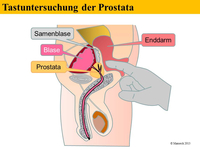

Im Allgemeinen spürt man den beginnenden Prostatakrebs nicht. Krankheitsspezifische Symptome werden erst in sehr späten Phasen der Erkrankung entwickelt. Um diese Symptome und die ernsthaften Folgen einer solchen Erkrankung zu verhindern, versucht man die Erkrankung frühzeitig zu diagnostizieren. Die wichtigsten diagnostischen Instrumente zum Nachweis eines Prostatakrebses sind die digital-rektale Untersuchung (DRU: Tastuntersuchung mit dem Zeigefingers des Arztes über den Enddarm), der PSA-Serumwert (ein Wert der durch eine einfache Blutabnahme ermittelt wird) und die transrektale Ultraschall-gesteuerte oder –gezielte Biopsie der Prostata.